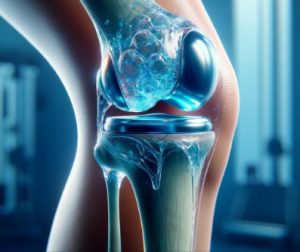

Total Eklem Değiştirme Cerrahisi Nedir?

Total eklem değiştirme cerrahisi, diğer adıyla eklem protezi ameliyatı, ileri derecede kalça veya diz ağrısı yaşayan hastalarda uygulanan en etkili tedavi yöntemlerinden biridir. Bu ameliyatın temel amacı; eklemdeki hasarlı veya aşınmış yüzeyleri yapay implantlarla değiştirerek, ağrıyı azaltmak, hareket kabiliyetini geri kazandırmak ve yaşam kalitesini artırmaktır. Eklemdeki kıkırdak doku yıllar içinde

Total Diz Protezi Nedir? Tedavisi Nasıl Yapılır?

Total Diz Protezi Nedir? Tedavisi Nasıl Yapılır?